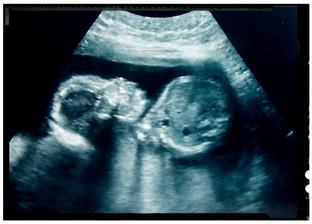

Dozvedela som sa to v júni keď mi tri dni pred ms začala rozprávať moja dcérka že mám v brušku bábätko. Tak som si urobila test až jeden deň pred tým ako mala prísť mrcha a zrazu dve čiarky. Tak sme sa hrozne tešili. Mysleli sme že termín bude marcový keďže v máji som mala ešte ms ale tak sme zistili že aj keď bola v máji mrcha tak už som bola tehu. Darmo máj lásky čas. Pohlavie sme sa dozvedeli v 16tt a druhý a posledný krát ho bolo vidieť 20tt. Od vtedy ssa schováva aj tváričku aj medzinozie 3D mi dr robil za každým na azdej poradni no ani jeden záber nič je to zrejme hanblivé bábätko . Tešíme sa už na neho budeme komplet